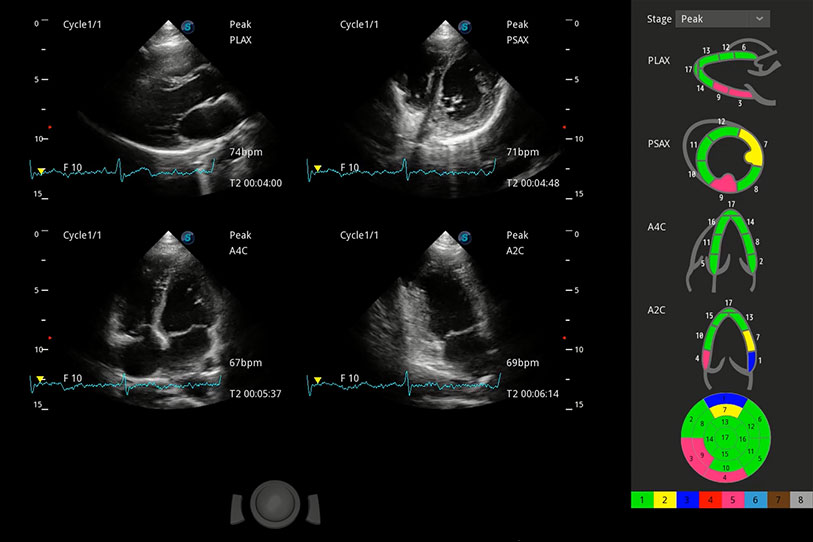

具備多種協(xié)議可選,同時(shí)支持17階段劃分法和專業(yè)的SE報(bào)告。

通過360度任意調(diào)節(jié)3條M型取樣線,在同一心動(dòng)周期上觀察心臟不同位置的運(yùn)動(dòng)曲線,得到準(zhǔn)確的心功能測(cè)量數(shù)據(jù),有效評(píng)估心肌運(yùn)動(dòng)及左心室功能。

實(shí)時(shí)用顏色表示心肌組織運(yùn)動(dòng),觀察和定量組織的運(yùn)動(dòng)情況,對(duì)快速檢測(cè)與評(píng)估心肌的灌注和活性、電傳導(dǎo)及心肌收縮和舒張功能等均能提供重要的診斷信息。